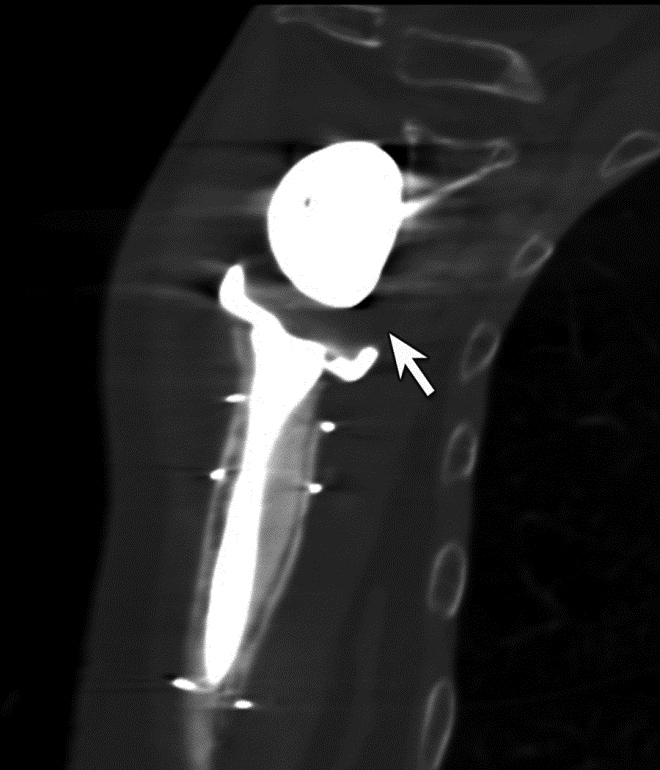

Just as with the immediate post-operative setting, CT is the modality of choice for evaluating complications related to spinal fusion. Screw fracture may occur in up to 25% of patients (Figure 13) (Ohashi, 2009; Lonstein, 1999). As with all cases of hardware failure, the imaging findings should be correlated with patient symptoms as not all hardware complications relate to current clinical symptoms. CT can be useful for the detection of polyethylene dislocation, which may occur in shoulder, hip and knee arthroplasties, and may be difficult to detect on radiographs (Figure 14) (Clarke, 2004).

Periprosthetic Fracture. (A) Coronal multiplanar reformation and (B) axial CT image of the right hip demonstrate radiographically occult non-displaced periprosthetic fracture involving the greater trochanter (arrow)

Polyethylene Liner Displacement. Sagittal multiplanar reformation of reverse total shoulder arthroplasty demonstrates posteriorly displacement of low attenuation polyethylene liner relative to the humeral component and glenosphere in patient with limited range of motion.